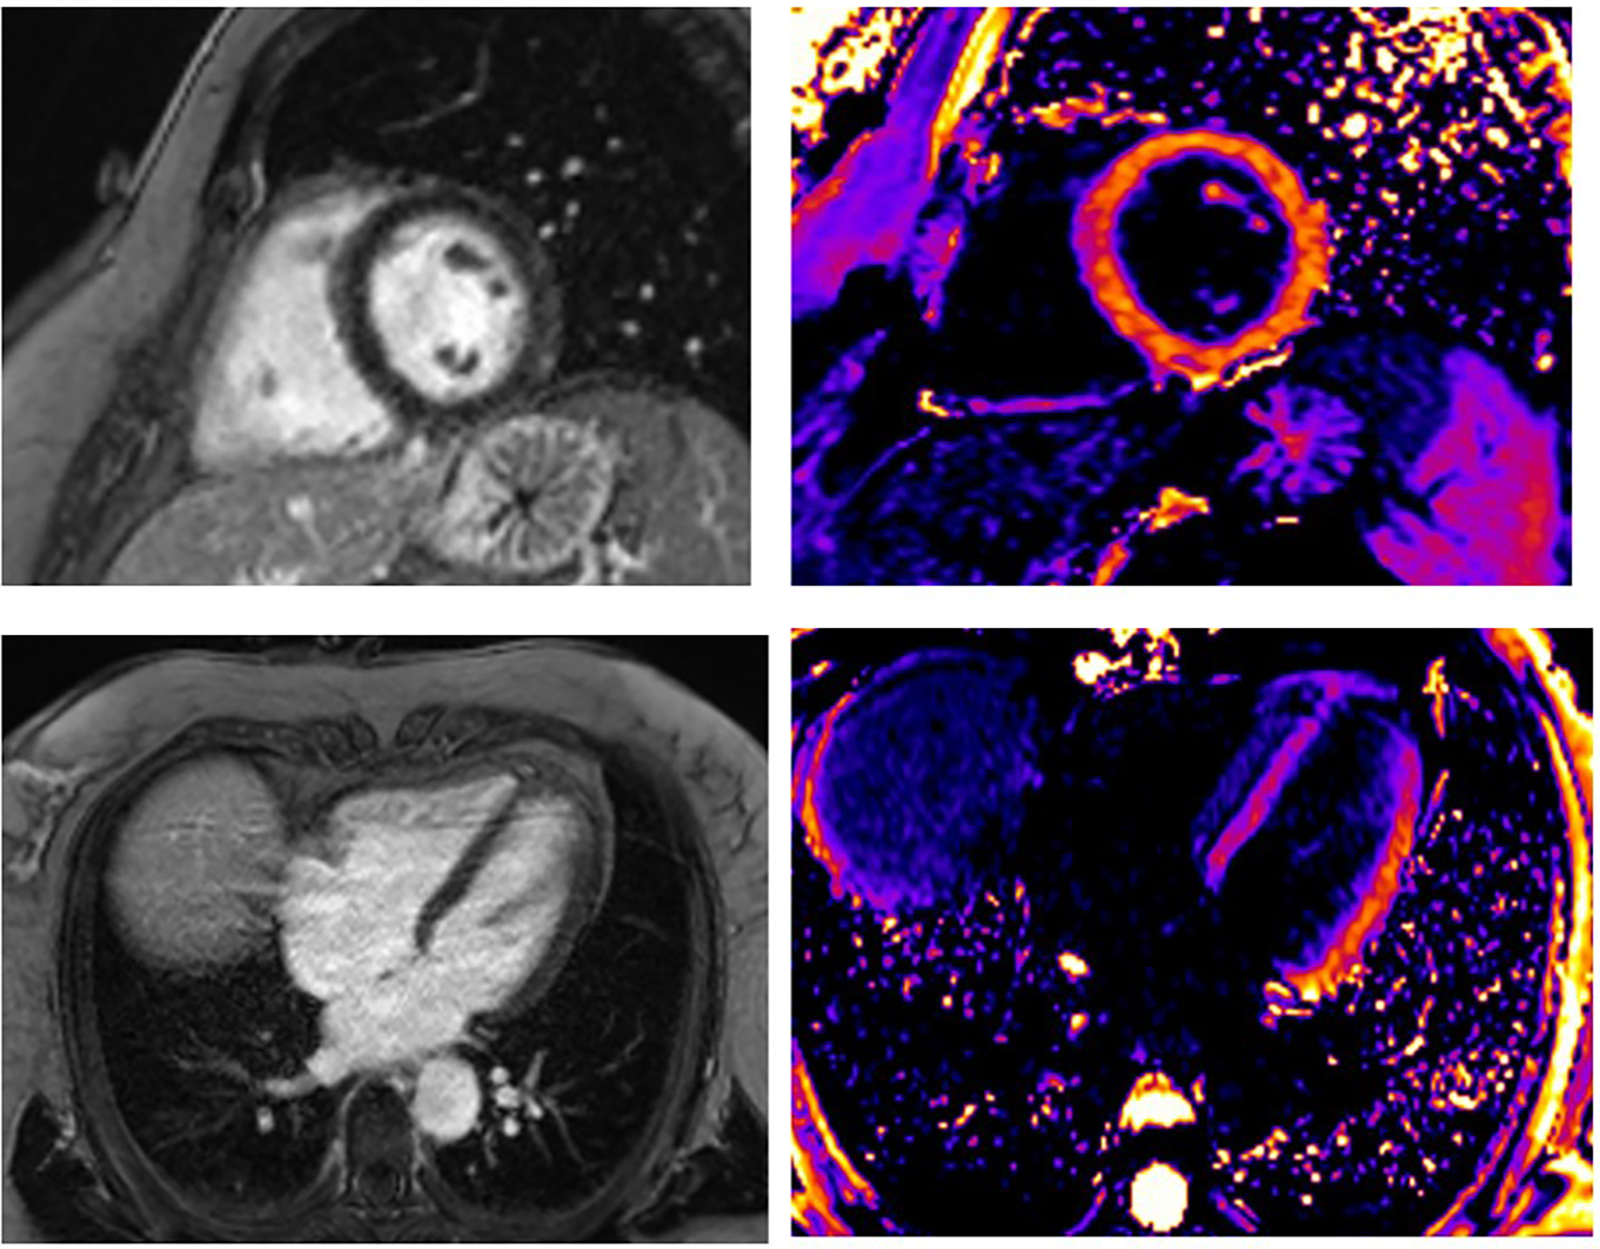

Figures 57 show GLS and regional longitudinal strain, providing valuable information on the mechanical deformation of the LV in three SCAD female patients before and after 1 month of follow-up.

FIGURE 5

www.frontiersin.org

Figure 5. A young woman presented with STEMI anterior localization and SCAD type 4 on the left anterior artery. She underwent treatment with PTCA. The baseline GLS and regional longitudinal strain were measured, and the baseline LVEF was found to be 38% (A). GLS and regional longitudinal strain in follow-up after 1 month were presented in one young woman in part (B). The control LVEF value was 48%.

FIGURE 6

Figure 6. The baseline GLS and regional longitudinal strain in one young woman with SCAD type 3 presented as STEMI anterior localization who was treated with PCI and implanted four stents. The baseline LVEF was 43% (A). The improved GLS and regional longitudinal strain were seen in the follow-up of the patient after 1 month (B). The control LVEF value was 53%.

FIGURE 7

Figure 7. Patient with SCAD type 2A of left anterior artery treated with medical therapy. The baseline LVEF was 52% (A). Slightly improved GLS and regional longitudinal strain were seen in the follow-up of the patient after 1 month (B). The control LVEF was 65%.

Figure 5 presents the GLS and regional longitudinal strain of a woman with SCAD of left anterior artery (LAD) type 4 and reduced LVEF at baseline and follow-up. She was treated with percutaneous transluminal coronary angioplasty (PTCA), and the figures depict the changes in her condition from baseline to the 1-month follow-up.

Figures 6A,B present the values of LVEF and GLS of a woman with SCAD of LAD type 3. She had mildly reduced LVEF on baseline (LVEF 43%), was treated with PCI, and had improved GLS and regional longitudinal strain after the 1-month follow-up. The LVEFs, GLS, and regional longitudinal strain are improved in the follow-up of these patients.

On the other hand, Figures 7A,B present the values of a woman with SCAD LAD type 2A treated only with medical therapy. She had preserved LVEF and slightly reduced GLS, without myocardial scar at baseline and after the 1-month follow-up. These parameters are also improved after the 1-month follow-up.

Based on the previous examples of various types and management of SCAD patients, it seems that the process of normalizing LV function could be complex and require further investigation.

Nevertheless, using advanced diagnostic echocardiography techniques, such as mechanical deformation and CMR assessment, can potentially provide significant benefits in monitoring SCAD patients.